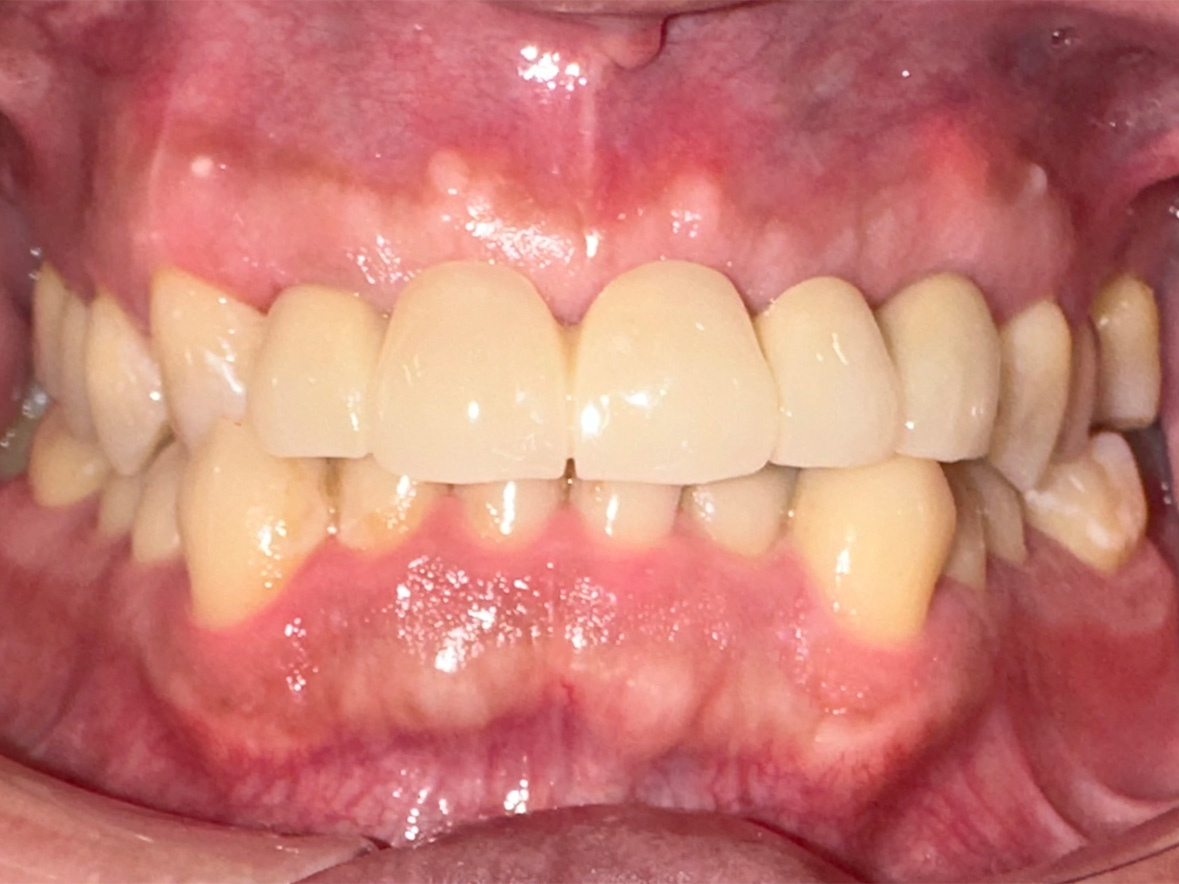

症例2

患者様の年齢 70代女性 主訴 入れ歯が痛い 噛みにくい 治療内容 上顎オールオン6

下顎臼歯部3本インプラント治療

抜歯即時インプラント埋入後3ヶ月の待機期間後、ジルコニアによる上部構造装着費用 456万円 治療期間・通院回数 6ヶ月/8回 デメリット・リスク 外科処置に伴う痛み・腫れ・出血・合併症の可能性があります。 -